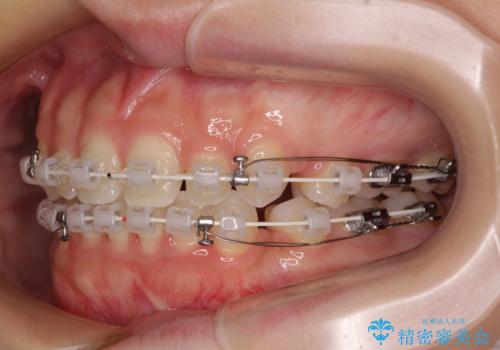

前歯のデコボコとクロスバイト ワイヤー装置での抜歯矯正

- 前歯のデコボコとクロスバイトを気にして来院された患者様です。

上下ともにデコボコはそれほど強くありませんでしたが、非抜歯では口元が突出した仕上がりとなる可能性があるため、上下左右の第一小臼歯4本を抜歯し、ワイヤー装置での抜歯矯正を行うこととしました

スペースを閉じるために期間を要しましたが、無事に綺麗な口元に仕上げることができました。